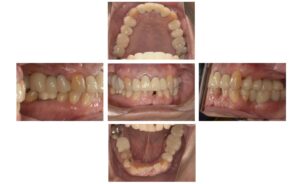

今回のインプラントは、かみ合わせに問題があったため、1年半かけてゆっくり咬合を作っていった症例です。

左下を放置していたことにより、左上45が伸びだしてきてしまい、左下がりの咬合平面になっています。また下前歯から左側にかけて態癖によるものと思われる歯の傾斜もあります。

そのせいか右側の臼歯部が悪化してきていて、右上の大臼歯は抜歯になりました。